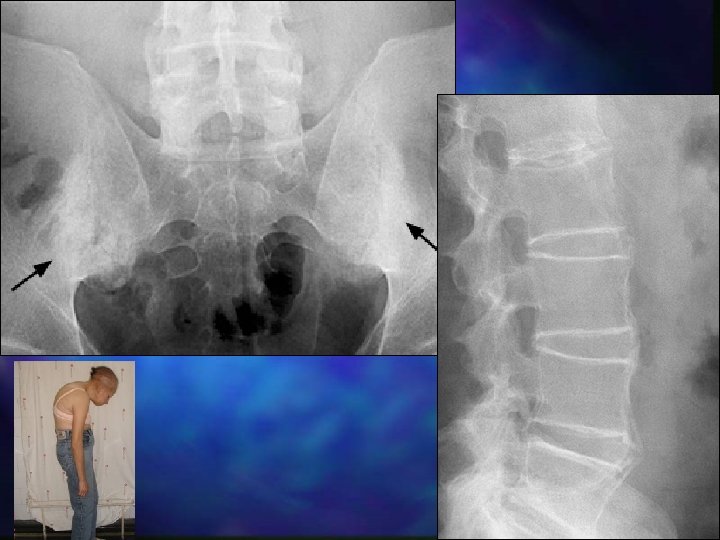

Espondilartrites Espondilite Anquilosante Artrite Associada com Uveíte Anterior (EA) Ea. P são um grupo de desordens reumáticas que compartilharm diversos Espondilartrites fatores comuns: Indiferenciadas 1. 2. Espondilartrites Artrite Psoriásica Artrites Enteropáticas Espondilartri tes Reativas Artrite Crônica Juvenil 3. Sinovites e entesites Associação similar com HLA-B 27 EA é o protótipo Gran J et al 1997; 36: 766 -71. Khan M Ann Int Med 2002; 136: 896 -907.

n Espondilite anquilosante, uma enfermidade reumática que provoca dores e inflamação na coluna vertebral, afeta em torno de 700 mil brasileiros. n Consultas públicas para inclusão de medicamentos de alta eficácia no combate a essas doenças foram feitas pela Secretaria de Ciência Tecnologia e Insumos Estratégicos do Ministério da Saúde no segundo semestre de 2004 e, passados mais de quatro anos, não há uma decisão. n Estimam-se aproximadamente 500 mil portadores da doença no País e num pequeno número de casos ocorre resistência aos tratamentos disponíveis no mercado. Para estes, em tempo recorde, foi incluído pelo Ministério da Saúde um novo antirretroviral (Raltegravir) na lista de distribuição gratuita do SUS.